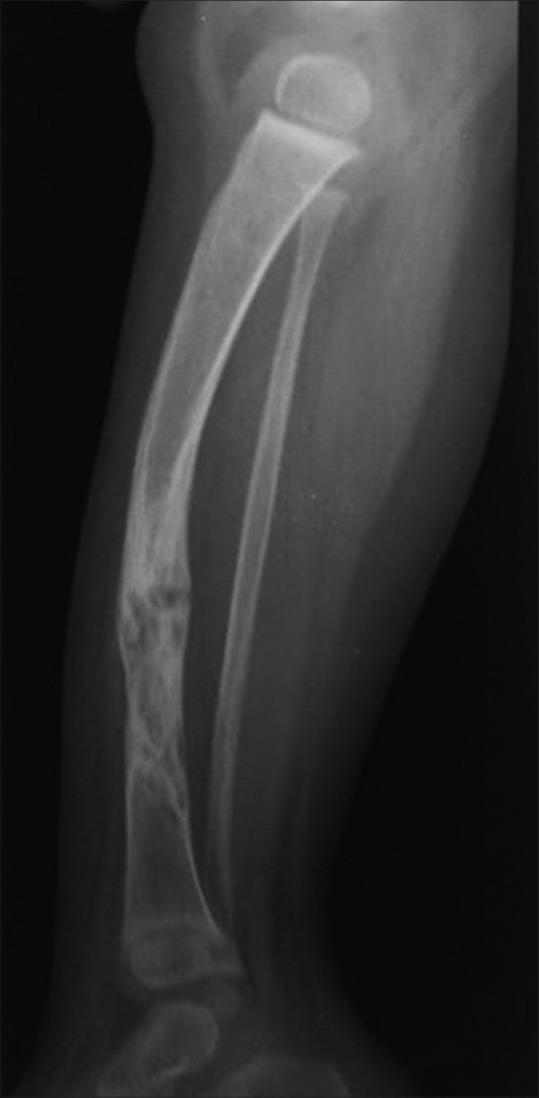

Phakomatoses or Neurocutaneous syndromes are a heterogeneous group of disorders and have variable inheritance pattern. Currently, more than 30 entities are included in this group. These disorders primarily affect the central nervous system; however, skin, viscera, and other connective tissues can also be involved with variable clinical presentation. We will describe and illustrate the various radiological findings of the common entities through the iconography of the cases presented to our department.

phakomatoses或神经皮肤综合征是一组异质性疾病,具有可变的遗传模式。目前,该组包括30多种疾病。这些疾病主要影响中枢神经系统;然而,皮肤、内脏和其他结缔组织也可能受累,临床表现各异。我们将通过提交至我科病例的影像学表现来描述和说明常见疾病的各种放射学表现。